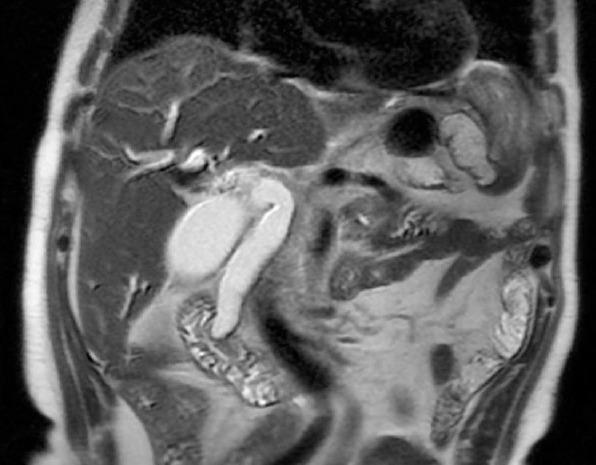

A 78-year-old male patient with a history of the right hemicolectomy due to the adenocarcinoma was admitted by the complaint of epigastric discomfort. Laboratory data showed an increase in liver biochemistries (aspartate aminotransferase (AST): 159 IU/L, alanine aminotransferase (ALT):235 IU/L, alkaline phosphatase (ALP): 350 IU/L, gamma-glutamyl transferase (GGT): 911 IU/L, total bilirubin: 1.55 mg/dl and direct bilirubin: 0.82 mg/dl). Endoscopic retrograde cholangiopancreatiography (ERCP) administered after the gastrointestinal (GI) upper endoscopy was compatible with the tumoral lesion, and biopsy confirmed 'neuroendocrine carcinoma'. Pylorus-preserving pancreaticoduodenectomy (PPPD) was performed with R0 resection. Pathologic evaluation revealed a 1,5 cm tumor of large cell neuroendocrine carcinoma (LCNEC). Five months later, biopsy of suspicious lesions in the liver was documented as 'high-grade neuroendocrine carcinoma metastasis'. He was referred to the oncology for chemotherapy, but, unfortunately, he expired three months later. Large cell neuroendocrine carcinoma (LCNECs) of the ampulla of Vater might have an aggressive clinical course despite radical resections involving lymph node dissections. Small tumor size and lymph node negativity are not reliable factors for this tumor type.

一名78岁男性患者,因腺癌行右半结肠切除术,因上腹部不适入院。实验室检查显示肝脏生化指标升高(天冬氨酸转氨酶(AST):159 IU/L,丙氨酸转氨酶(ALT):235 IU/L,碱性磷酸酶(ALP):350 IU/L,γ-谷氨酰转移酶(GGT):911 IU/L,总胆红素:1.55 mg/dl,直接胆红素:0.82 mg/dl)。上消化道内镜检查后进行的内镜逆行胰胆管造影(ERCP)与肿瘤病变相符,活检确诊为“神经内分泌癌”。行保留幽门的胰十二指肠切除术(PPPD),切缘R0。病理评估显示为1.5 cm大细胞神经内分泌癌(LCNEC)肿瘤。五个月后,肝脏可疑病变活检记录为“高级别神经内分泌癌转移”。他被转至肿瘤科进行化疗,但不幸的是,三个月后去世。尽管进行了包括淋巴结清扫在内的根治性切除,Vater壶腹大细胞神经内分泌癌(LCNEC)仍可能有侵袭性的临床病程。肿瘤体积小和淋巴结阴性对这种肿瘤类型来说并非可靠因素。